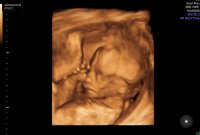

Congrats, I didn't ask a gender, I nearly did but held it together lol.I had my private gender scan yesterday at 17 weeks. We are team pink yay! so happy! i was so shocked when we popped the balloon i was so sure it was a boy. They did glimpse of 4d and it was amazing.

Awwww such a beautiful baby @Shezza84uk

Thank you, I can’t wait to meet her.Awwww such a beautiful baby @Shezza84uk